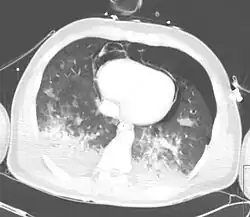

| A CT scan showing a pulmonary contusion (red arrow) accompanied by a rib fracture (purple arrow) | |

Computed tomography

Computed tomography (CT scanning) is a more sensitive test for pulmonary contusion,[8][38] and it can identify abdominal, chest, or other injuries that accompany the contusion.[43] In one study, chest X-ray detected pulmonary contusions in 16.3% of people with serious blunt trauma, while CT detected them in 31.2% of the same people.[50] Unlike X-ray, CT scanning can detect the contusion almost immediately after the injury.[48] However, in both X-ray and CT a contusion may become more visible over the first 24–48 hours after trauma as bleeding and edema into lung tissues progress.[51] CT scanning also helps determine the size of a contusion, which is useful in determining whether a patient needs mechanical ventilation; a larger volume of contused lung on CT scan is associated with an increased likelihood that ventilation will be needed.[48] CT scans also help differentiate between contusion and pulmonary hematoma, which may be difficult to tell apart otherwise.[52] However, pulmonary contusions that are visible on CT but not chest X-ray are usually not severe enough to affect outcome or treatment.[42]